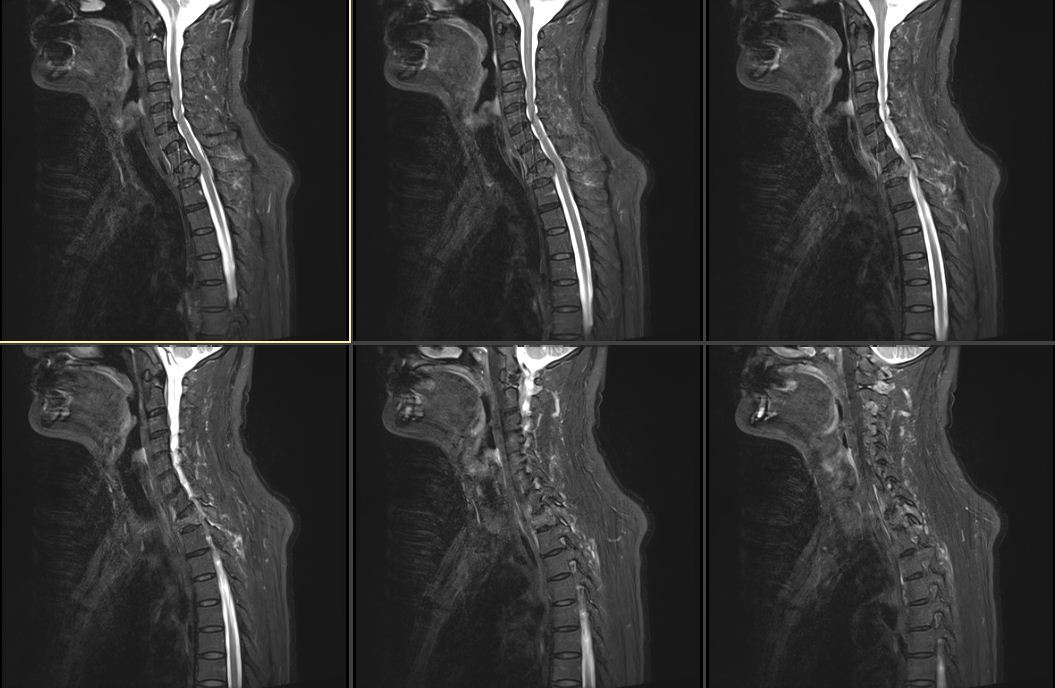

入院后,胸椎增强磁共振示胸6-8椎体层面椎管后缘梭形异常信号-考虑髓